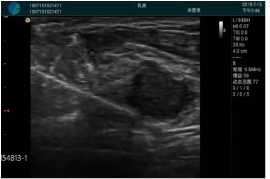

M20查看:囊內回聲均勻,邊界清晰,囊壁光滑

M20引導抽吸術后囊腫消失,原區(qū)域空腔形成,脂肪層與腺體層架構發(fā)生改變

病例二:

甲狀腺囊性結節(jié),囊壁鈣化,透聲好

甲狀腺囊性占位